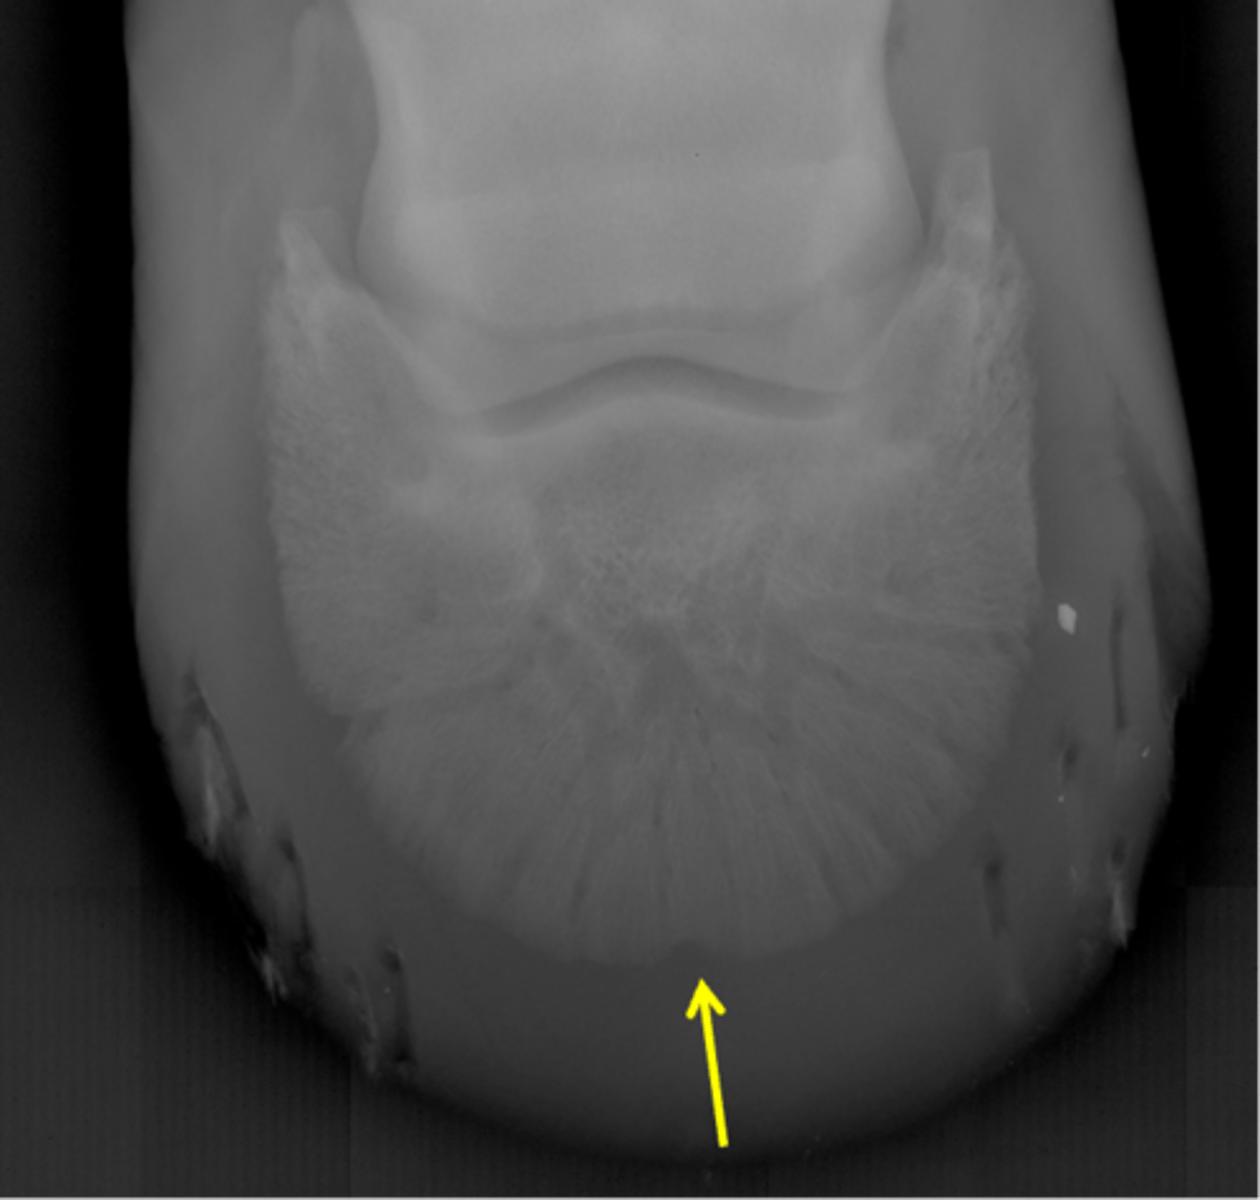

Navicular bone

Flexor cortex

Navicular bone

Proximal border of navicular bone

Distal border of navicular bone

Synovial invaginations

Flexor skyline

What view is this?

1. Flexor surface

2. Corticomedullary distinction

3. Number of synovial invaginations

What is the flexor skyline used to evaluate?